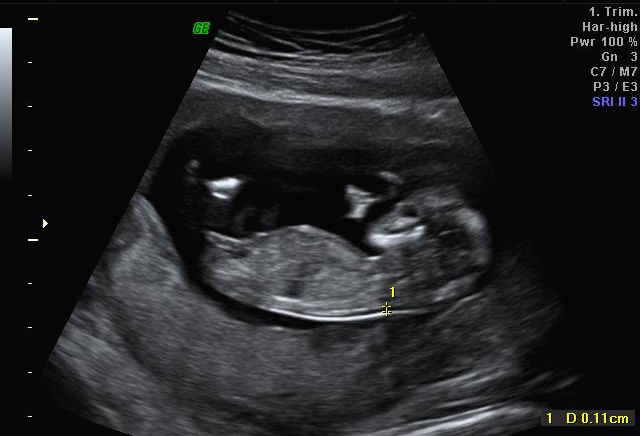

그리고 초음파 봐주시는 분께서 13주차가 되면 정확히 알 수 있으니 다음 주에 오라고 하셔서 일주일 뒤 다시 방문을 했습니다. (위에 사진은 12주 차 때 아들이라고 보여주신 초음파 사진이에요~ 화살표 보면 툭 튀어나와있는 부분을 보여주면서 아들이라고 하셨어요~)

아 진짜 전문가는 다르구나~ 이렇게 이른 주수에도 성별을 알 수가 있구나 생각을 했지만 이 시기 때는 성별을 정확히 알 수 없다는 글들을 봐서 살짝~ 의심스럽기도 했지만 그래도 100프로라니깐 ㅎㅎ 믿어보았어요~ 근데 위에 사진을 보면 성별을 알 수 있는 각도 법이 있는데 각도가 딸 같아서 긴가민가~하긴 했지만 의심은 잠시! 전문가 분을 믿기로 ㅋㅋㅋㅋ

한 달 뒤인 17차 때 다시 사설로 가서 초음파 검사를 받았는데 검사해주시는 분 께서 한참을 보시더라고요~ 그러면서 어떻게 보면 딸 같다고 하셔서... 응? 100프로 아들이라 해서... 다 아들껄로 준비하고 있는데.. 무슨 소리지? 하고 다시 한번 봐달라고 하니 아들이라 하시면서 위에 초음파를 보여주셨어요!

위에 아들이라 했던 초음파 사진은 다 딸 초음파 사진이니 성별이 궁금하신 분들은 딸 초음파 사진으로 참고해서 보시면 좋을 것 같아요~그리고 전 결혼 5년 만에 가진 첫 아이라 설레는 마음에 너무 이르게 아이 용품들을 준비했는데 출산 2~3달 전에 준비해도 늦지 않은 것 같아요~ 혹시 저처럼 성별 반전이 있을 수 도 있으니 아이 용품은 천천히 준비하시길~~!